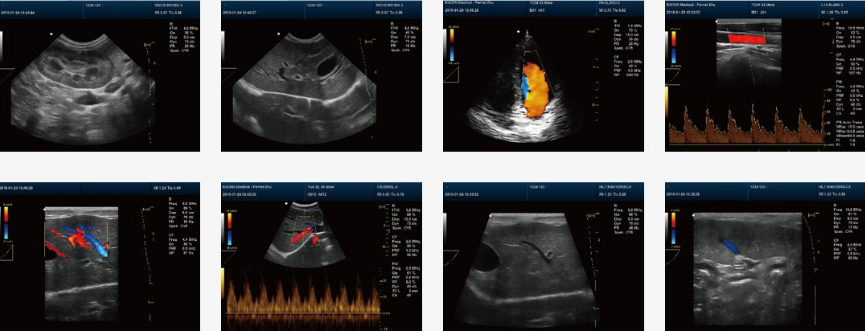

应用影像诊断来断定和描述肝肿瘤特征: 典型的肝细胞癌和血管肉瘤呈现为一个大的单独的团块,肝左叶是肝细胞癌的长发位置,由于坏死核或空泡腔的存在,团块能够是空腔的,因此很难和肝脓肿等分开。 超声波检查可对肿瘤进展定位并确定肿瘤开展的阶段,术前的诊断也要求在超声波指点下进展活检,超声波检查法对有腹水的动物尤其有用。 犬猫的原发性恶性肝胆管肿瘤预后不良,经过积极治疗可存活一年或更长,猫恶性肿瘤平均存活0.1-4个月,恶性肿瘤的转移率高且侵袭程度大,所以大多数患病动物不能经过手术切除而治愈,良性肿瘤可经过手术进展切除,术后存活12-44个月不等。